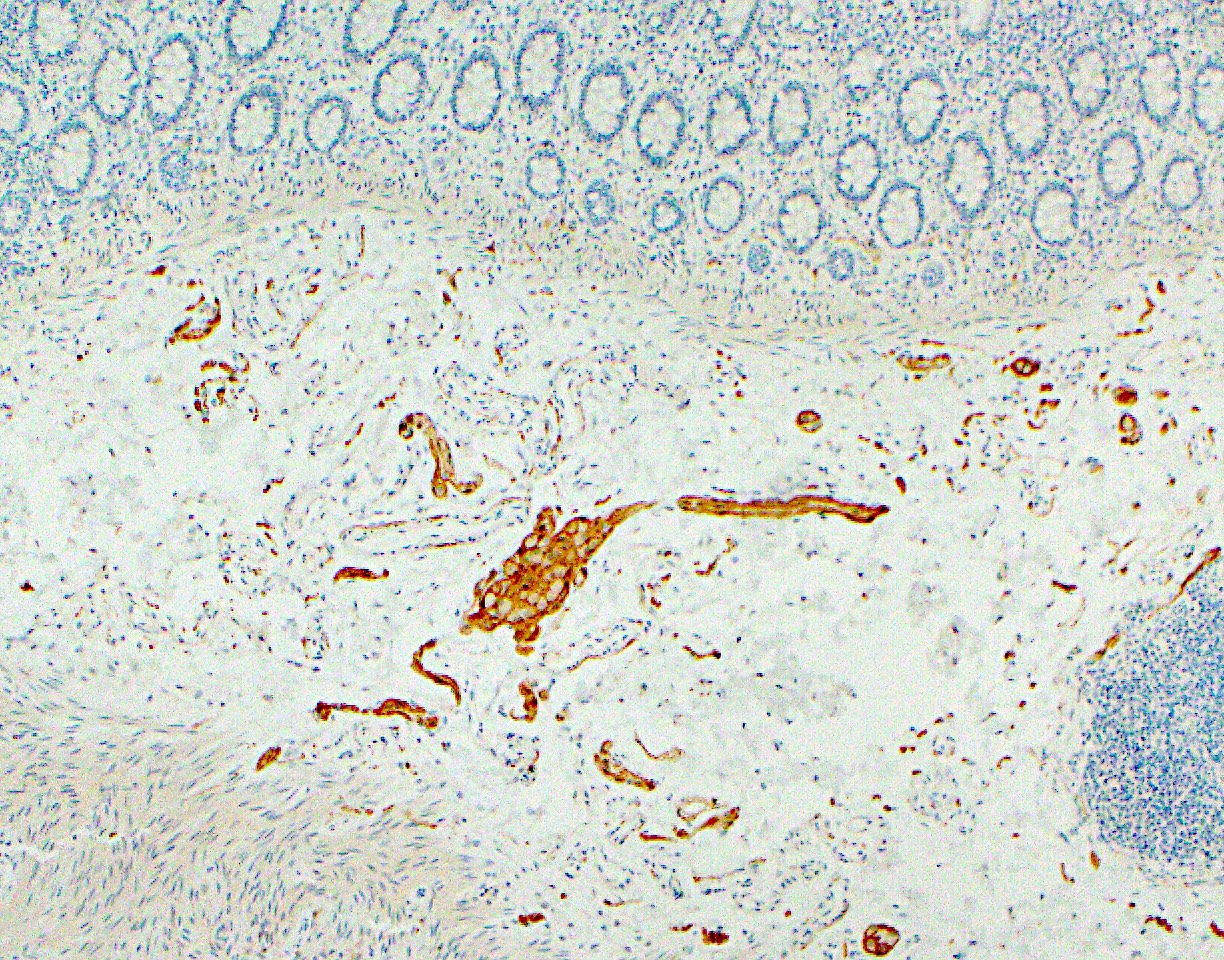

Microscopic (histologic) images

Positive stains

- Enterocytes (absorptive cells): pankeratin AE1 / AE3, CK20, CDX2, SATB2 and villin

- Goblet cells: MUC2, depending on their surface or crypt location in the mucosa; periodic acid Schiff (PAS), PAS diastase (PASD), mucicarmine and Alcian blue also stain the mucin in goblet cells (Histopathology 2000;37:561)

- Enteroendocrine cells: synaptophysin, chromogranin, neuron specific enolase (NSE) and pankeratin AE1 / AE3

- Paneth cells: AE1 / AE3

- Interstitial cells of Cajal: KIT

- Muscularis mucosae and propria: desmin, vimentin, SMA

- Ganglion cells: calretinin

- Enteric glial cells: S100, GFAP, synaptophysin, PDGFRA (R), neuron specific enolase (NSE)

- Inflammatory cells:

- Lamina propria T lymphocytes: CD3+ / CD4+

- Intraepithelial T lymphocytes: surface - CD3+ / CD8+ and TCRαβ+; near lymphoid follicles - CD3+ / CD45RO+ (Chem Immunol 1998;71:1)

- Lamina propria plasma cells: CD138, MUM1 and CD79a

- Macrophages: CD68, CD163, HAM56, MAC387, lysozyme and alpha-1 antitrypsin

- Mast cells: KIT, tryptase